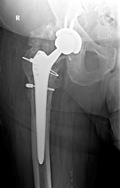

Patient had already had 2 revisions of the right hip, but noted increasing pain and shortening of the leg. Xray revealed prosthesis was loose and sinking into the femoral bone.

Hip was reconstructed with osteotomy of the greater trochanter, removal of the loose prosthesis, reconstruction and bone grafting with a taper type revision stem and refixation of the greater trochanter.